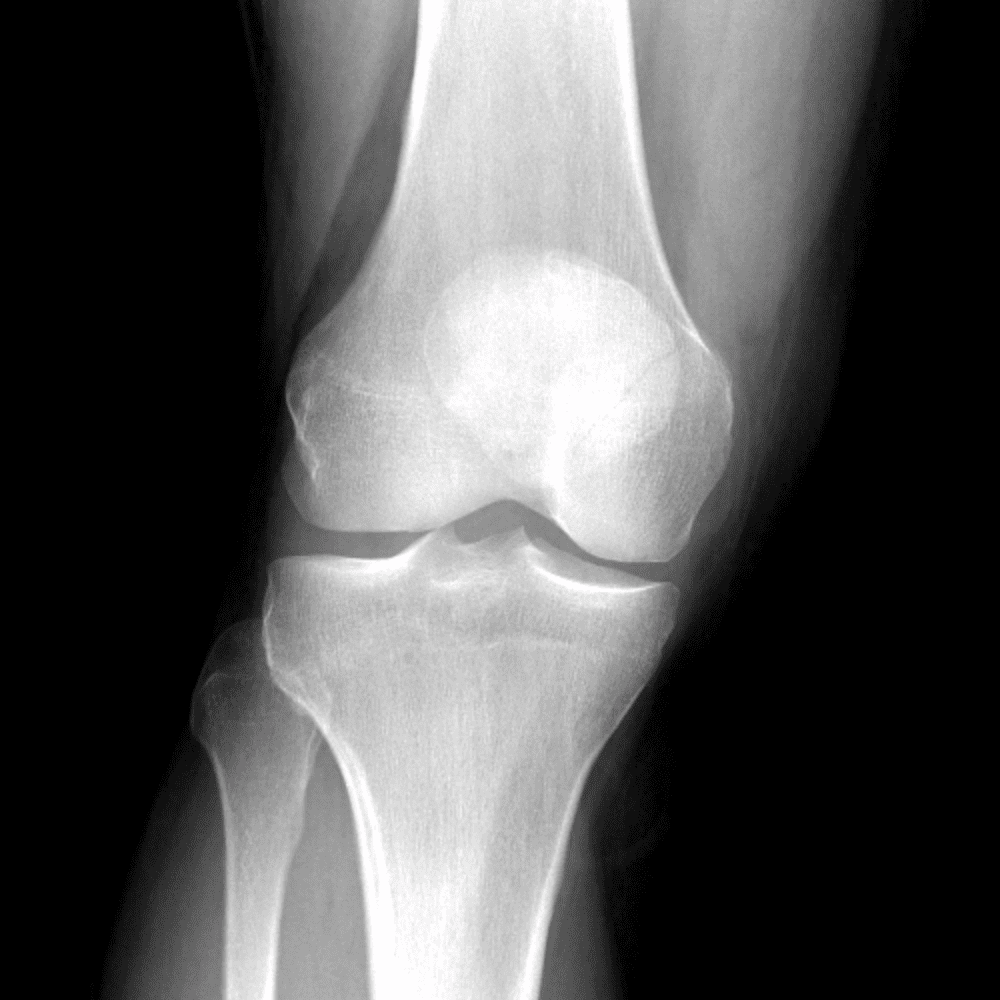

Simula o plantão incluindo casos sutis ou difíceis e alguns normais.